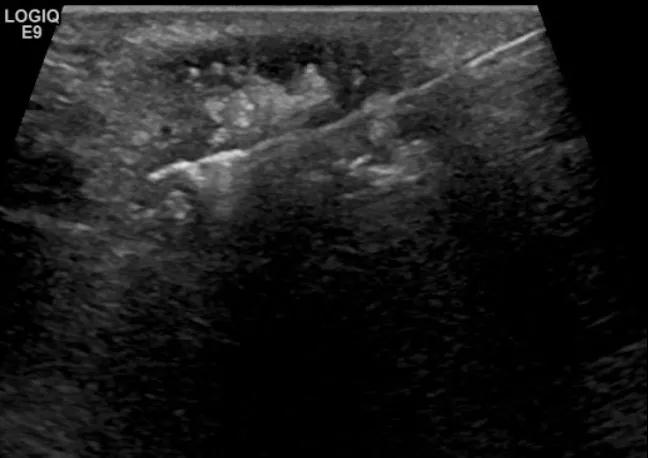

第三例是甲状腺癌患者,双侧甲状腺癌切除术后、碘治疗后一年余效果欠佳,超声显示左颈3区3枚低回声结节,穿刺示甲状腺乳头状癌转移。患者不愿意手术,希望采取局部治疗。对病灶进行液体隔离后采取热消融术,由于淋巴结较小,热消融一分钟左右完全灭活,术后增强影像显示没有脏器充填。

(病例3图例)